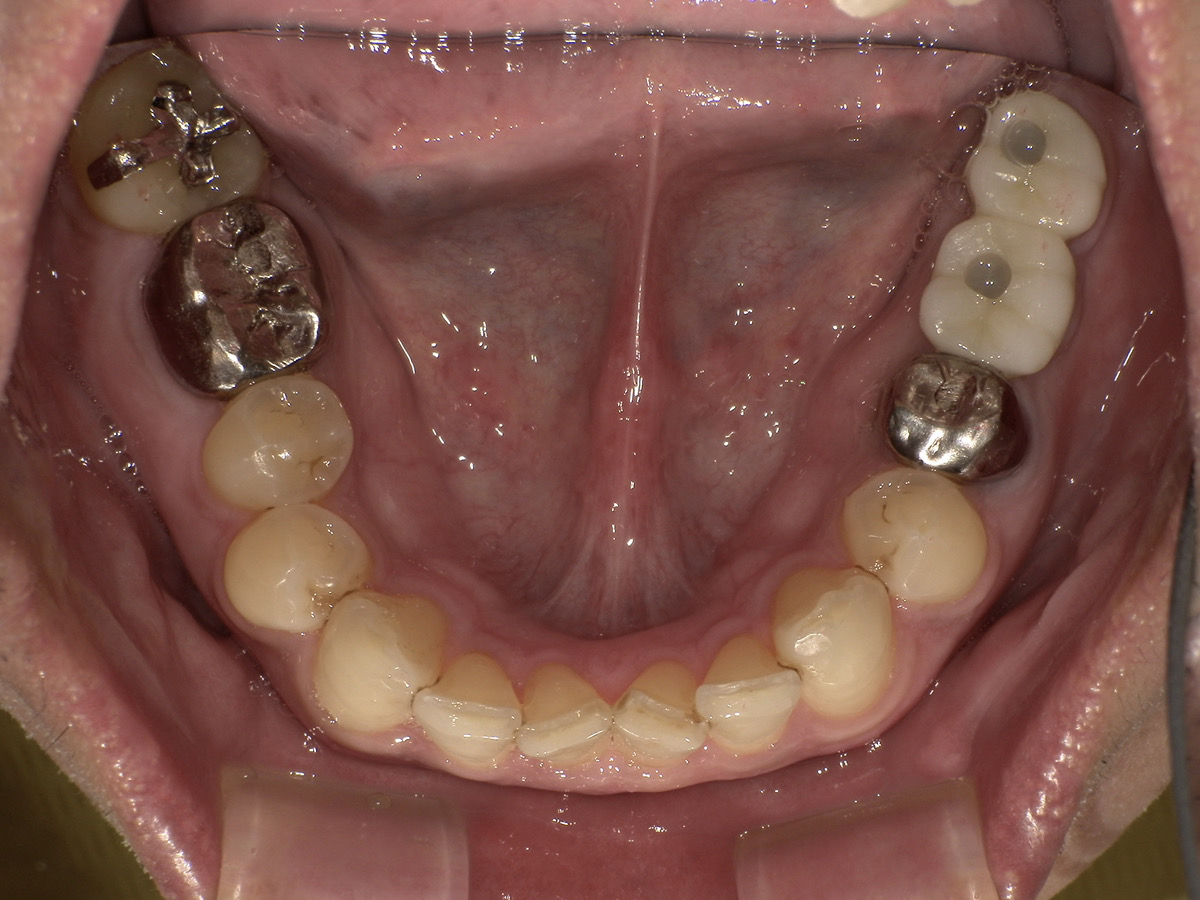

治療後

| 年齢・性別 | 40代・男性 |

| 期間 | 9か月 |

| 費用 | 1,067,000円。保証はインプラントオペ後1年目〜3年以内は院内保証(インプラント料金に込み)がありますが、4年目以降は別途費用がかかりますが保証は可能です。任意保証になりますので金額は患者さんが選ぶ保証によって変わります。 ※患者さんの口腔内の状態によってインプラント治療の金額は異なります。 |

| 治療内容 | 左下7番がむし歯により状態悪く抜歯後、ギシだと両側の歯を削っての作製で、健康な歯を削る事が気になるので元々欠損していた左下6番と一緒に2本分インプラントで進めていきたい。 |